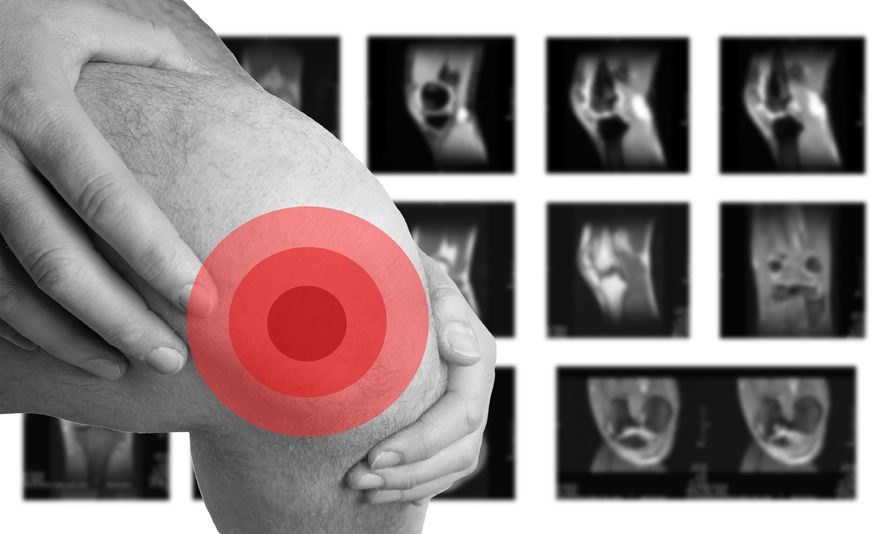

膝关节积液是滑膜炎诱发的表现,因为人的关节中本身存在像润滑油一样的液体,能够减少关节与关节之间的摩擦,正常情况下,关节积液量适中才能维持关节的正常运转。

但因为炎症的影响,膝关节积液问题就发生了,如果是少量轻度的膝关节积液,患者大多觉察不到异常,只有通过核磁共振等检查才能明确。 可如若积液数量,患者往往会有关节疼痛,红肿发热等症状,并且还伴随着膝关节屈伸受限表现。